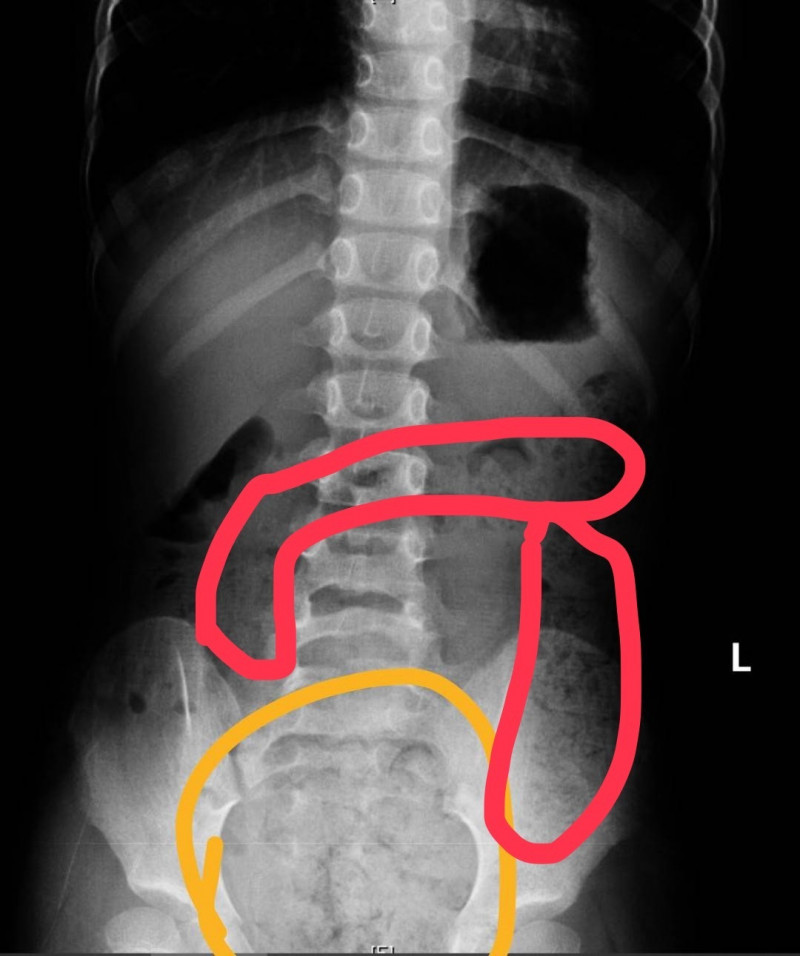

〔記者黃良傑/高雄報導〕高雄一名11歲小五男童因腹痛、冒冷汗、嘴唇發紫、手腳冰冷被送急診,經問診、觸診及腹部X光檢查後,診斷為便秘,經灌腸後解出很多大便,症狀終於緩解,媽媽說兒子習慣邊大便、邊玩手機,原本從從容容進廁所,因被罵上太久又匆匆忙忙沖馬桶,自己也不清楚有無大乾淨!

阮綜合醫院另也收治一名6歲女童,她的肚子痛得直哭叫,腹部明顯異常脹大,經腹部X光檢查發現她"一肚子大便"!原來剛上小學,可能還未習慣上下課時間,憋便到連幾天沒上大號,也記不清楚,直到嚴重腹痛才送急診。

阮綜合急診兒科主治醫師蕭宇超表示,2童都屬小兒「功能性便秘」,即排除生理結構與疾病問題,因排便、飲食習慣或心理因素所造成的便秘,當孩童一個月內,每周排便少於3次,腹脹且解便時疼痛、糞便過硬或過粗,就是便秘了。